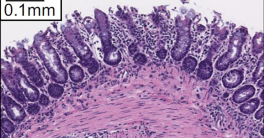

Health & BehaviorResearchers from UC San Diego found that children diagnosed with metabolic dysfunction-associated steatotic liver disease (MASLD) are at significantly increased risk of premature death and serious long-term health complications. The study, which followed 1,096 children over an average of 8.5 years.